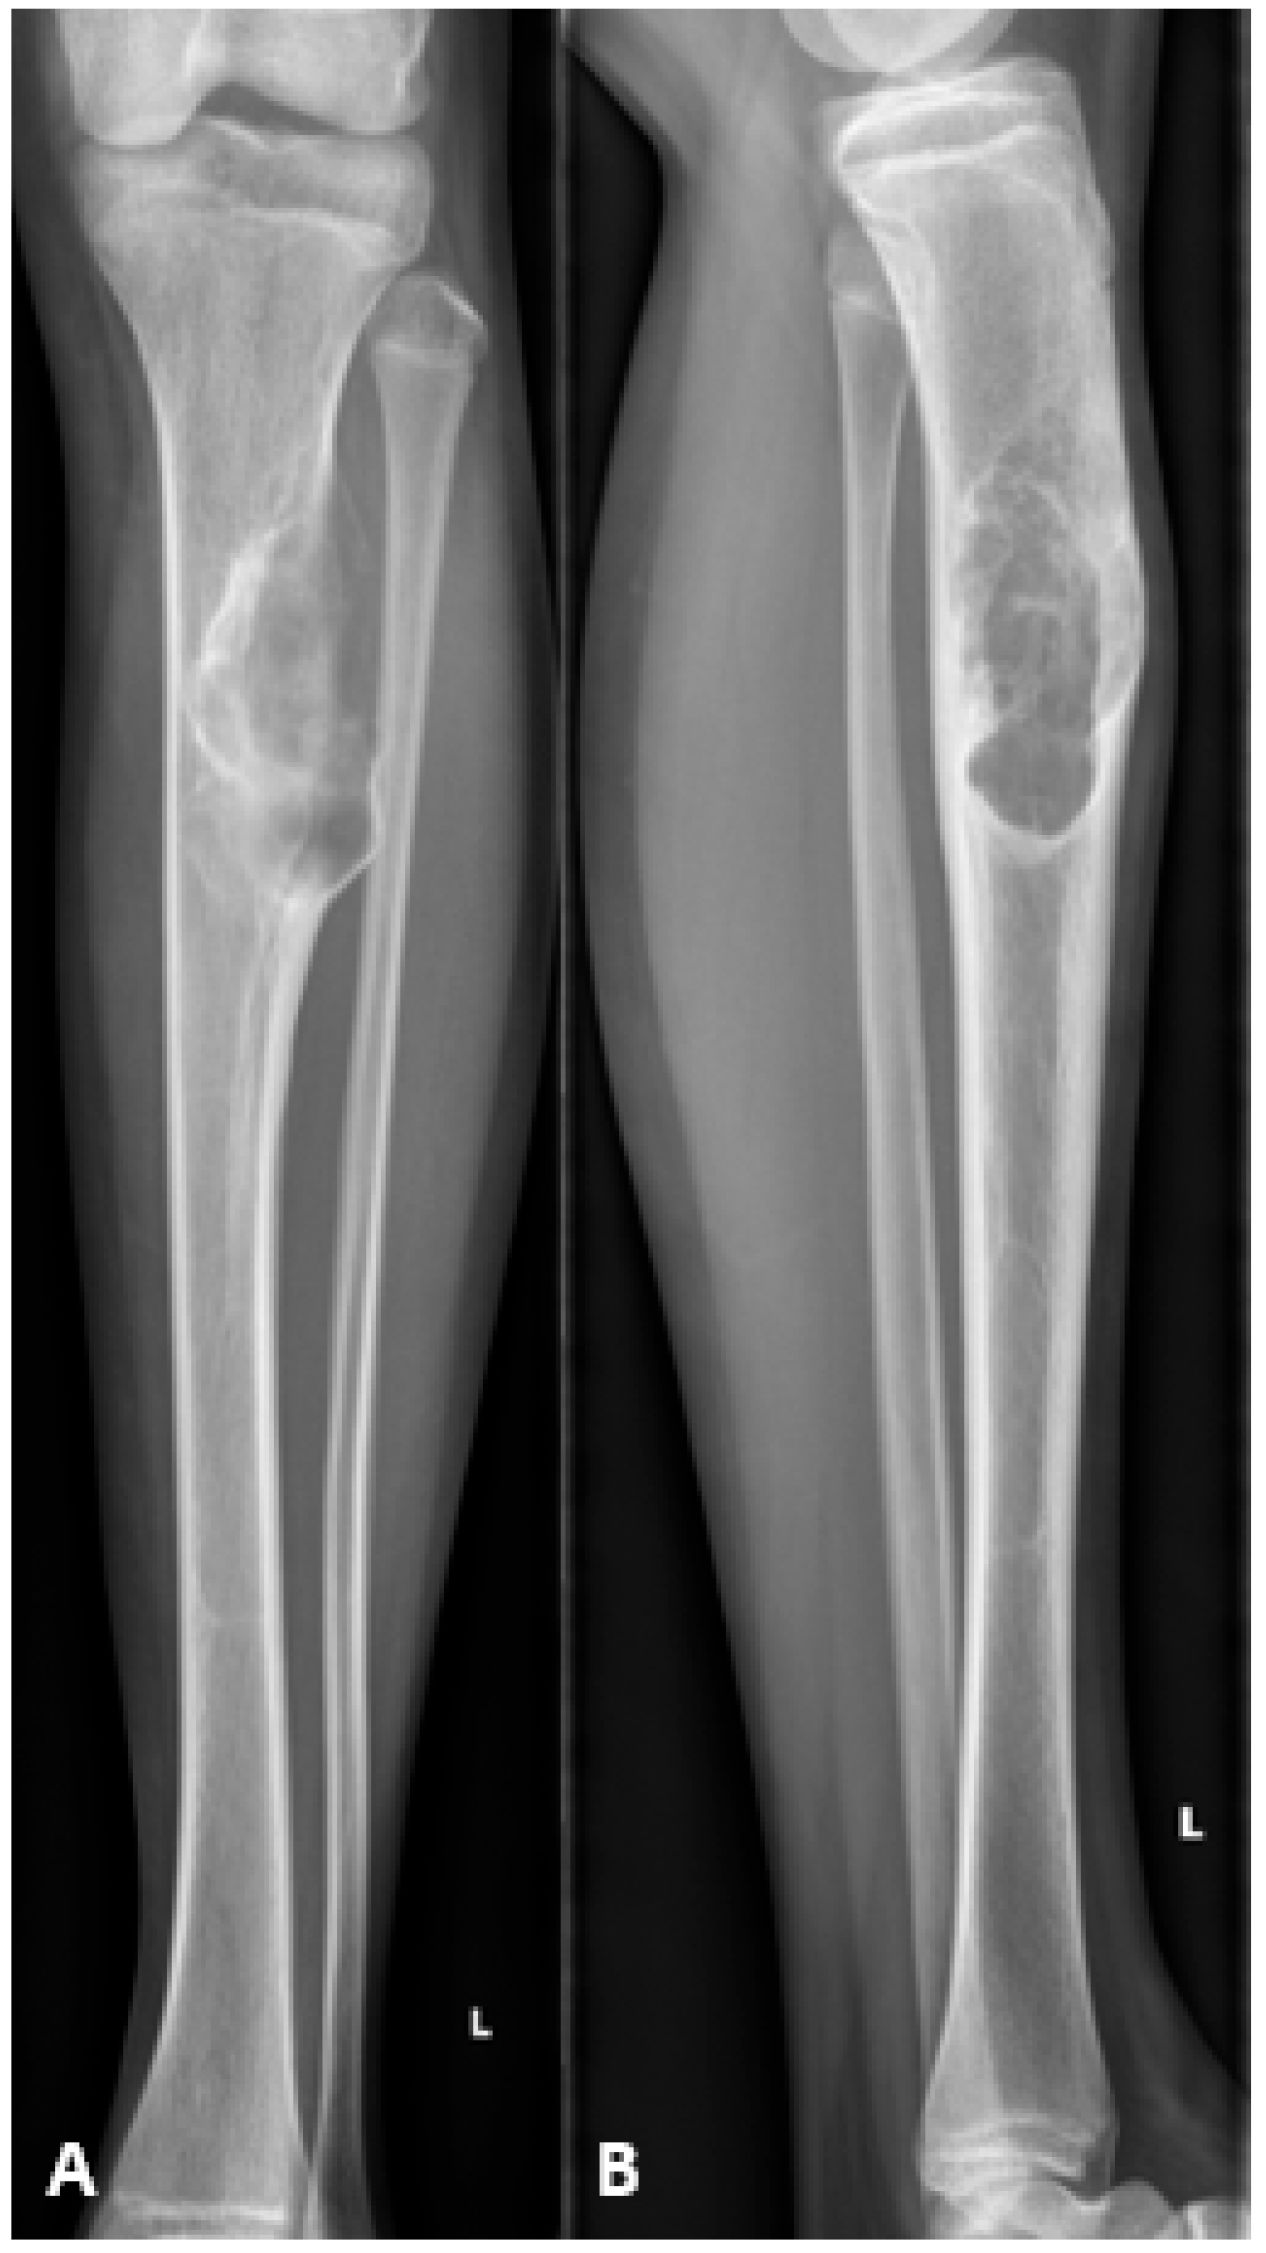

At 18 months postoperatively, radiographs confirmed complete consolidation at both the docking and distraction sites (Figure 7). At two years postoperatively, complete hardware removal was performed (Figure 8).

Figure 8.

Radiographs following hardware removal, showing anteroposterior view (left) and lateral view (right) of the tibia. Slight procurvatum and varus alignment are noted.